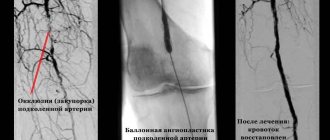

Ангиография – рентгеноконтрастный метод исследования, применяется в условиях стационара, для уточнения локализации процесса и выбора метода оперативного вмешательства. Метод высоко информативен, но так как в амбулаторной практике он не применяется, подробно останавливаться на нем мы не будем.

1 и 2А стадии ХАНК всегда подлежат консервативному лечению. При наличии 2Б стадии, а также при ХАНК 3 стадии, пациента следует направить на консультацию к ангиохирургу для решения вопроса о целесообразности хирургического лечения. В настоящее время применяются шунтирующие и протезирующие операции, а также поясничная симпатэктомия (эффективность последнего метода в последнее время оспаривается многими авторами). Все большее признание получает стентирование.

Особую сложность представляет лечение трофических расстройств в виде язв на фоне 3 А-Б стадии ХАНК или критической ишемии нижней конечности. У таких пациентов постоянно присутствует болевой синдром, язвы плохо очищаются, зачастую при самом адекватном и настойчивом лечении отмечается прогрессирование некротического процесса в конце концов приводящее к ампутации. Все пациенты с трофическими расстройствами должны быть проконсультированы ангиохирургом для решения вопроса о возможности выполнения реконструктивной операции на сосудах или стентирования. Если такую операцию удается выполнить, это существенно улучшает гемодинамику в конечности, что значительно ускоряет заживление язвенных дефектов. Противопоказаниями к реконструктивным операциям обычно являются: поражение дистального сосудистого русла, исключающее возможность наложения шунта, тяжелая сопутствующая патология, дающая высокий операционно-анестезиологический риск вмешательства. В такой ситуации, при наличии соответствующих условий (небольшая протяженность стеноза и др.), может быть выполнено стентирование как малоинвазивный и достаточно безопасный метод.